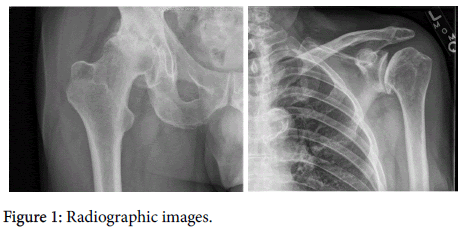

Degree of OA severity was performed by two of the investigators to ensure interpreter reliability. The Kellgren-Lawrence numeric scale (on scale of 1 to 4) for grading knee OA was used [10]. This global visual radiographic assessment based on osteophytes, cysts, subchondral sclerosis, and joint space narrowing is most widely used for OA of the knees but is also commonly used in the assessment of other synovial joints [11]. In this review, the scale was applied to the hip and shoulder digital radiographic images (Figure 1).

arthritis-Radiographic

Figure 1: Radiographic images.